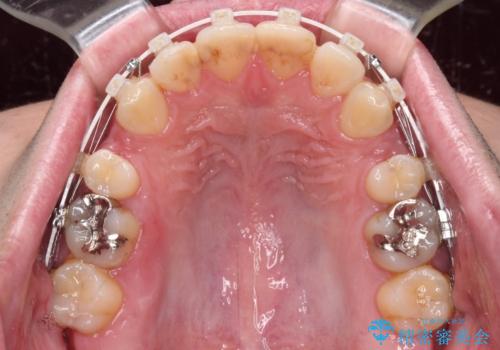

- 口がうまく閉じられないとのことで来院された患者様です。

上下唇をしっかり合わせようとすると、顎先が前方に突出してしまうほど口が閉じにくい状態でした。

口元の突出感を改善するために上下左右の第一小臼歯4本を抜歯し、ワイヤー装置にて矯正治療を行うこととしました。

また、上下前歯は舌の突出癖による開咬となっていたため、舌のトレーニングを徹底するよう指示しました。

舌突出癖の改善トレーニングは、仕上がり、治療期間、そして治療後の後戻りに大きな影響を及ぼします。

トレーニングをしっかりと行っていただいたため、スッキリとした口元に仕上がりました。